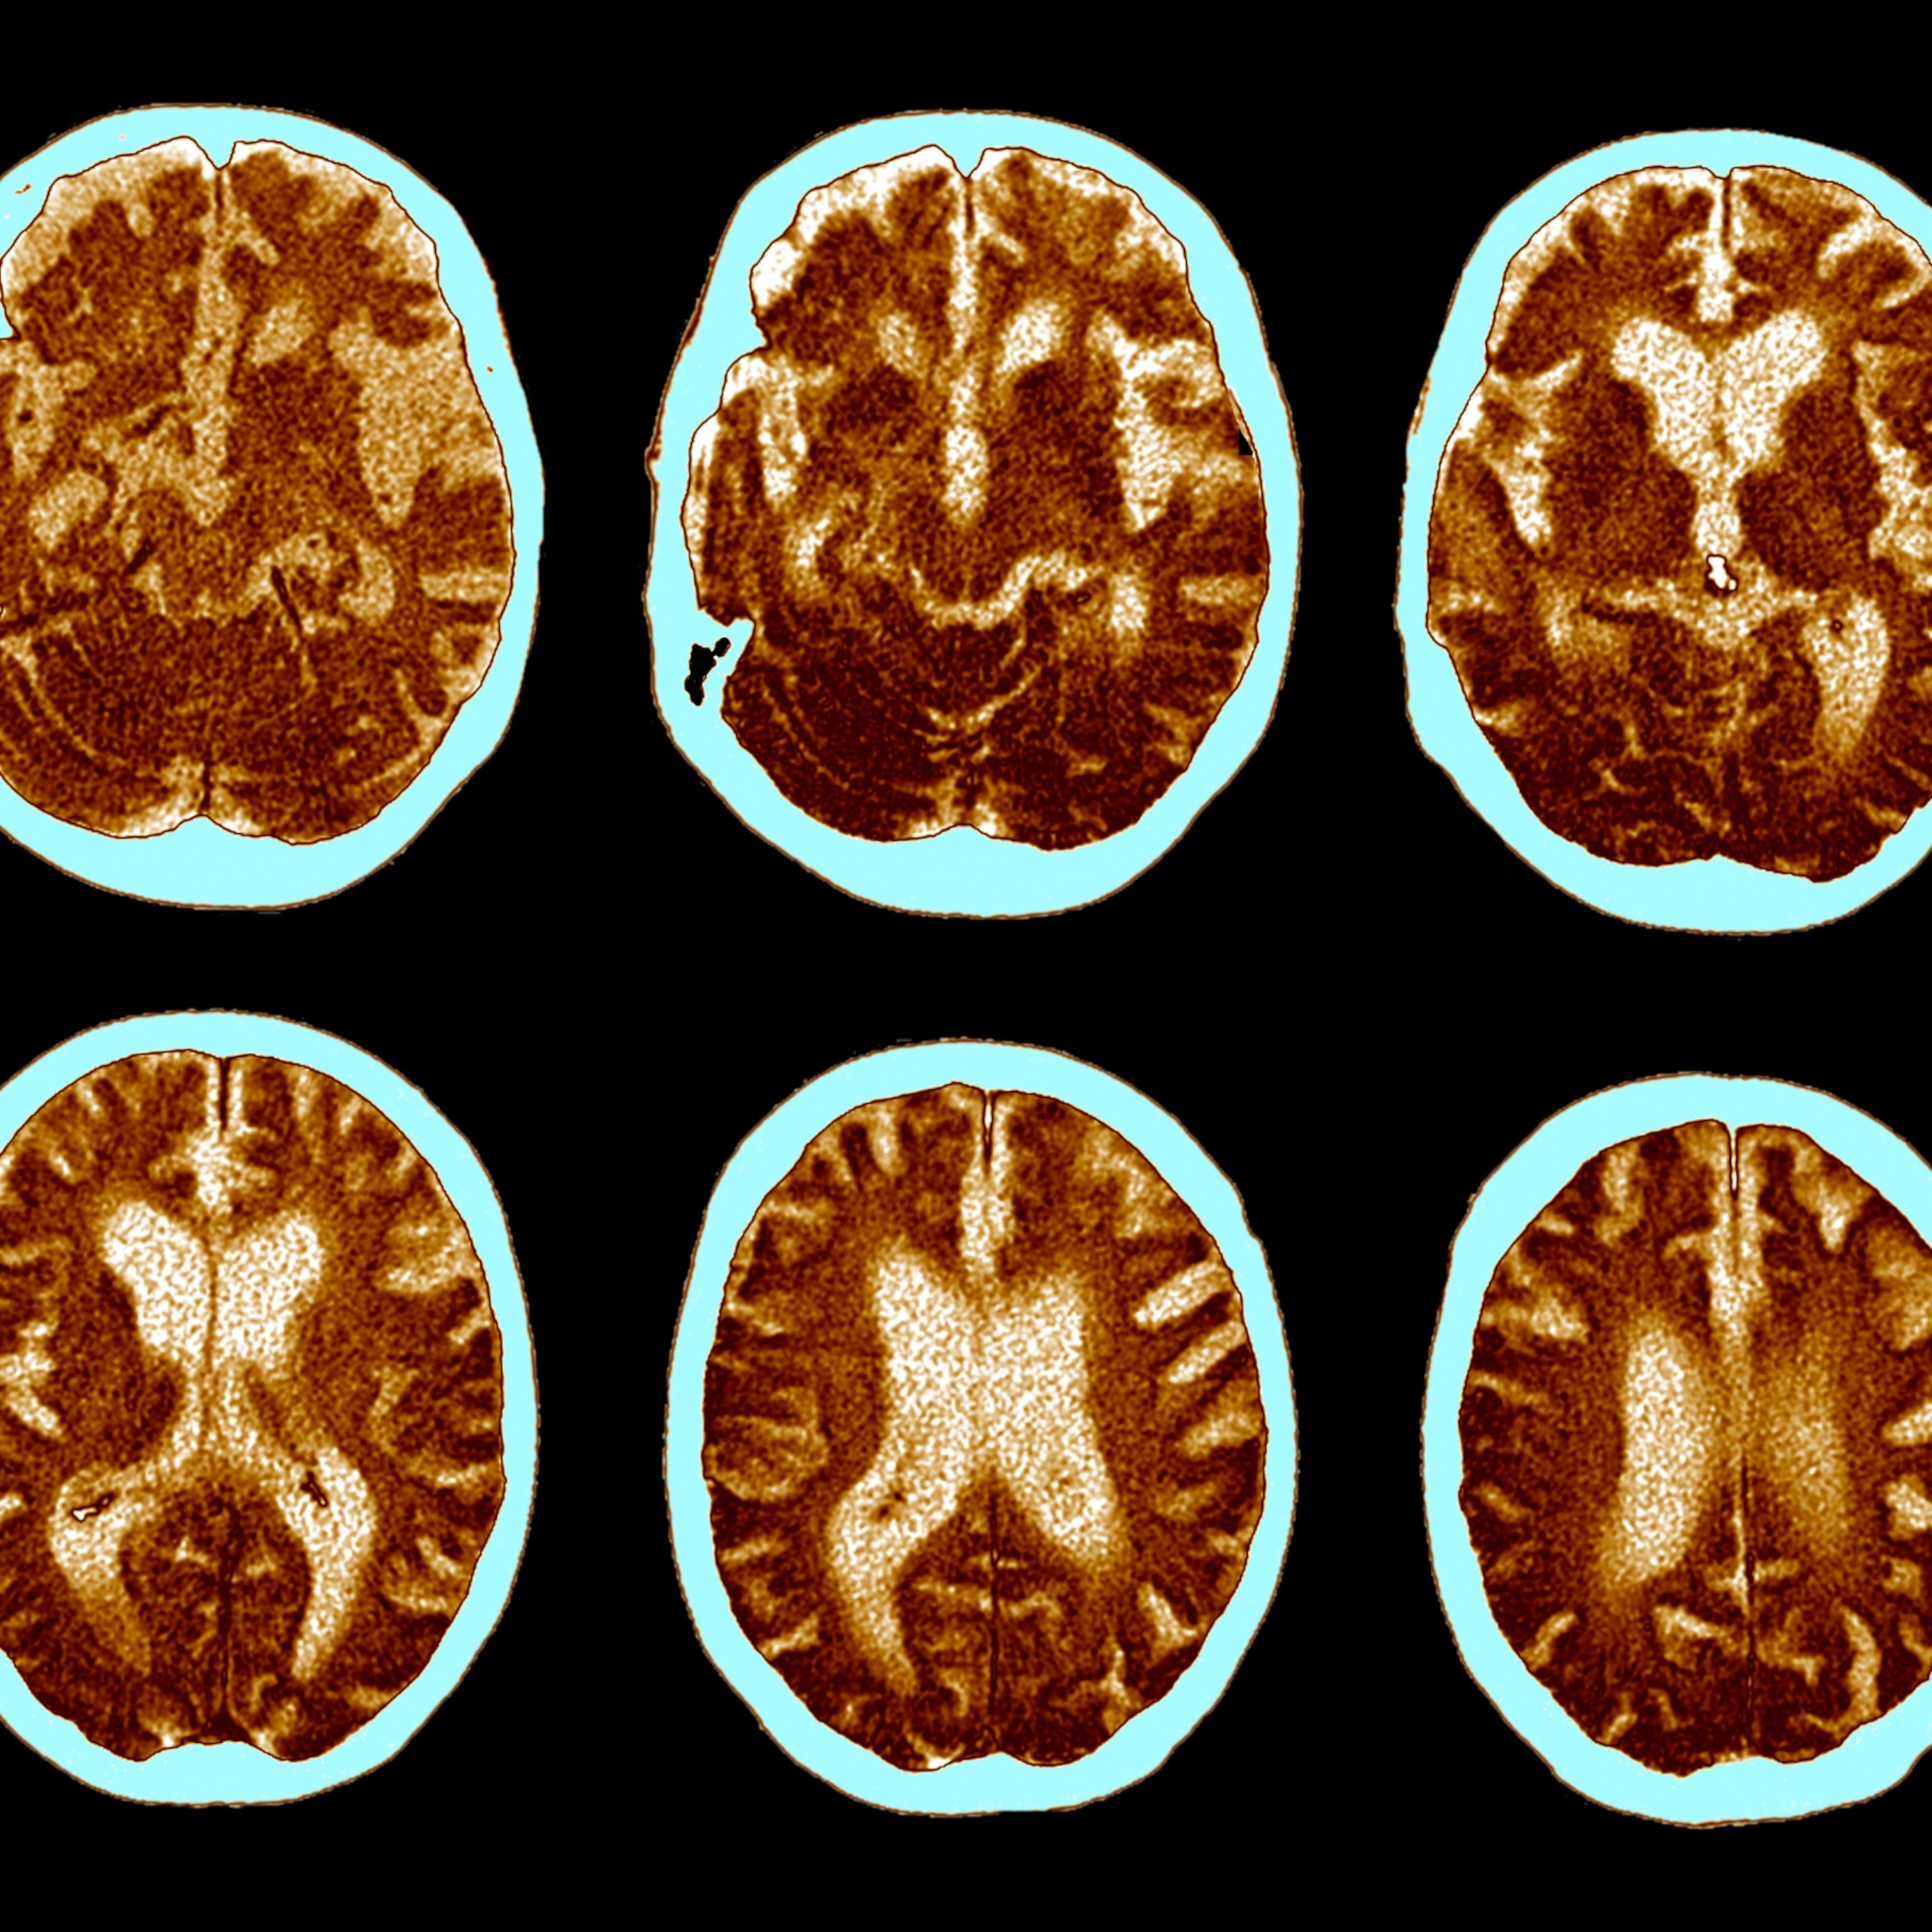

Although research shows the brain loses about 5 percent of its volume per decade after age 40, scientific findings suggest that picking up a new skill—like learning a musical instrument—can help preserve brain function well into our golden years.

Why our brains shrink with age

The gradual loss of brain tissue, known as brain atrophy, can begin as early as our 30s, "but it doesn’t happen to everyone at the same rate,” says Daniel Gustavson, a cognitive psychologist at the University of Colorado Boulder.

When it does occur, atrophy often affects key areas like the prefrontal cortex, which is responsible for problem solving and adaptability, and the hippocampus, which governs memory and spatial navigation.

Brain shrinkage is largely driven by the loss of neurons and specialized junctions in the brain called synapses, as well as a reduction in plasticity—the brain's ability to adapt and reorganize. Another contributing factor is the age-related decline in production and efficiency of neurotransmitters like dopamine, serotonin, and acetylcholine—a chemical messenger critical to memory and muscle movement. As these neurotransmitters decline, so does mental sharpness.

To make matters more complex, both gray and white matter also diminish with age. These nerve tissues play critical roles in protecting and supporting neural connections. Their deterioration can lead to a variety of symptoms, the severity of which often depends on genetics and lifestyle, says Golnaz Yadollahikhales, a neurologist at Cedars-Sinai Medical Center in Los Angeles.